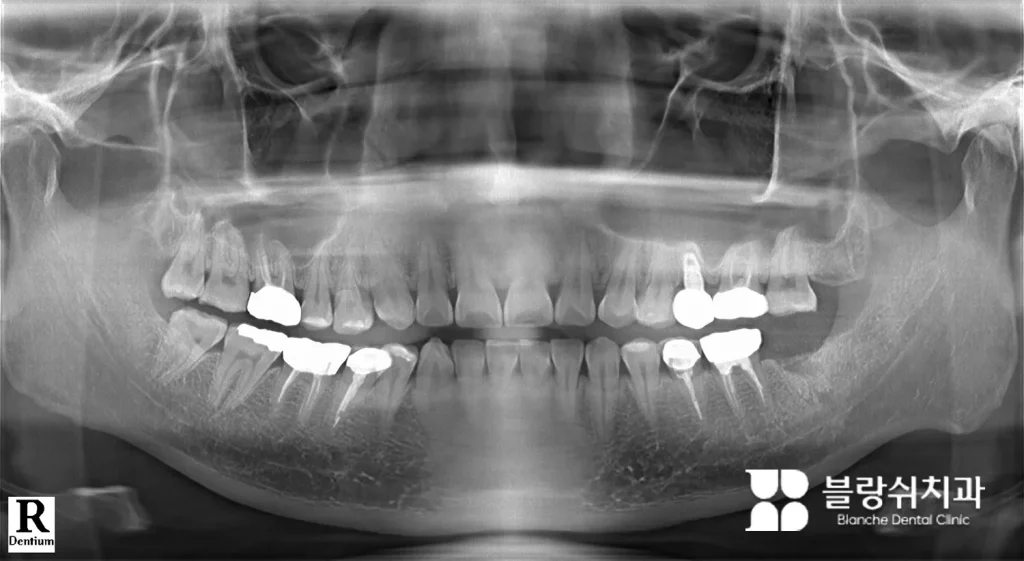

(4) 염증이 심한 어금니 발치 후 합성골 뼈이식(GBR)

보통 블랑쉬치과에서는 뼈이식을 최소화하려 하지만, 불가피한 경우에는 진행하고있습니다. 아래는 그 예시 사례입니다.

환자분은 좌측 하악(아래턱) 맨 끝 어금니에 염증이 심한 상태로 내원하셨습니다. 정밀 CT 촬영 결과, 해당 부위는 신경관과의 거리가 가까워 임플란트를 바로 심기엔 위험 요소가 있었습니다.

이에 따라, 발치와 동시에 뼈이식(GBR)을 진행했습니다. 이때 사용된 이식재는 Sorbone 0.25cc 합성골로 자가골보다 통증이 적고 뼈 부피 유지력이 뛰어나 만족도가 높았습니다.

이번 사례는 신경 손상 예방과 임플란트 위치 확보를 위해 선제적 뼈이식이 필요한 케이스였습니다. 시술 후 안정적으로 뼈가 형성되었고, 이후 임플란트를 정확한 위치에 식립할 수 있었습니다.

뼈이식 후에는 이렇게 엑스레이로 확인할 수 있습니다. 이식 재료는 뼈처럼 하얗게보이며, 상악동 거상술 부위는 동그랗고 하얗게 나타납니다.